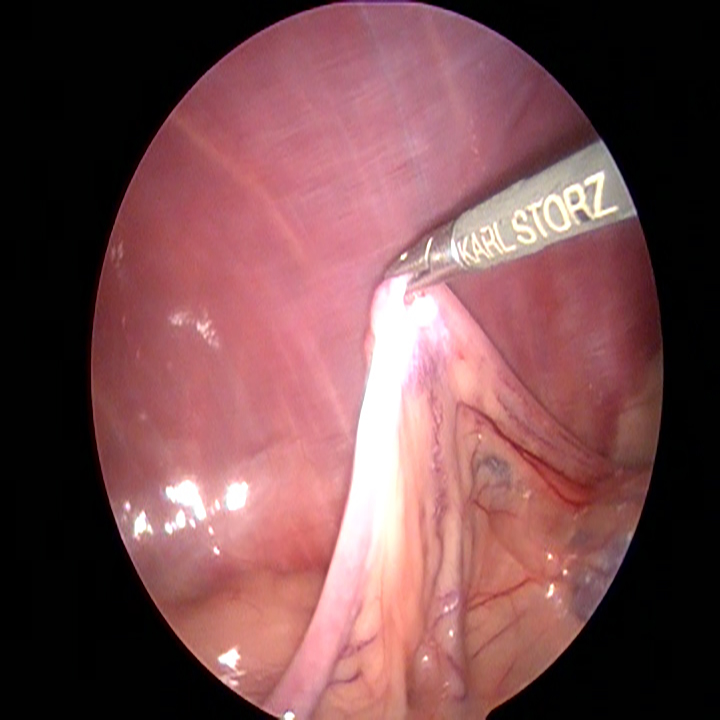

Als eerste wordt er een gaatje in de buik gemaakt, waarlangs met een naald CO2 in de buik gebracht kan worden. Als de buik hiermee voldoende is opgeblazen wordt er een trocar net achter de navel ingebracht. Hierna brengen we via deze trocar de scoop (een soort camera) naar binnen. Ook wordt hier tijdelijk de CO2 toevoer op aangesloten. Vervolgens kunnen we met de scoop kijken of alles er goed uitziet en kunnen we het plaatsen van de andere trocars in de gaten houden. We brengen nu een trocar net voor de navel in. Tenslotte brengen we een grote puntige trocar in, een stukje voor het bekken. De plaatsing van deze trocar is ook de reden dat we een lege urineblaas willen hebben.

Wanneer alle trocars geplaatst zijn, kantelen we de operatietafel naar voren en leggen we de patiënt op haar zij. Dan gaan we op zoek naar de linker eierstok. Doordat de milt eroverheen ligt kan dit soms wat meer moeite kosten. Eenmaal gevonden, branden we de ophangbanden en bloedvaten van het ovarium door. Hierbij moet ervoor gezorgd worden dat er ver genoeg van de nieren en de buikwand af gewerkt wordt, om hitteschade te voorkomen. De eierstok wordt via het gat bij het bekken verwijderd. Na het controleren van de plek waar de eierstok verwijderd is en na het opnieuw plaatsten van de achterste trocar, wordt de andere kant gedaan.